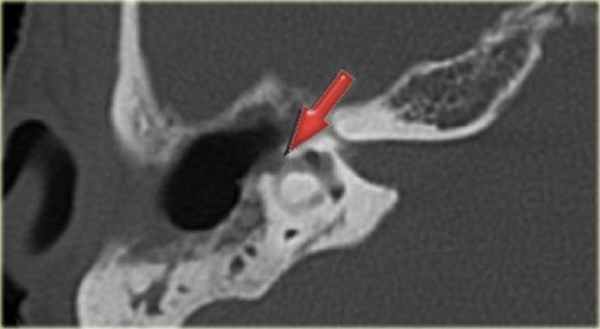

КТ-картина дефекта латерального полукружного канала (фистула)

вследствие холестеатомы у 53-летней пациентки с клиникой головокружения

- Томография. На КТ височной кости при фистуле лабиринта может визуализироваться небольшой овальный или круглый дефект. Это исследование показано при невозможности провести дифференциацию с другими патологиями, используя ранее собранные данные. При необходимости дополнительно назначают МРТ височной области.